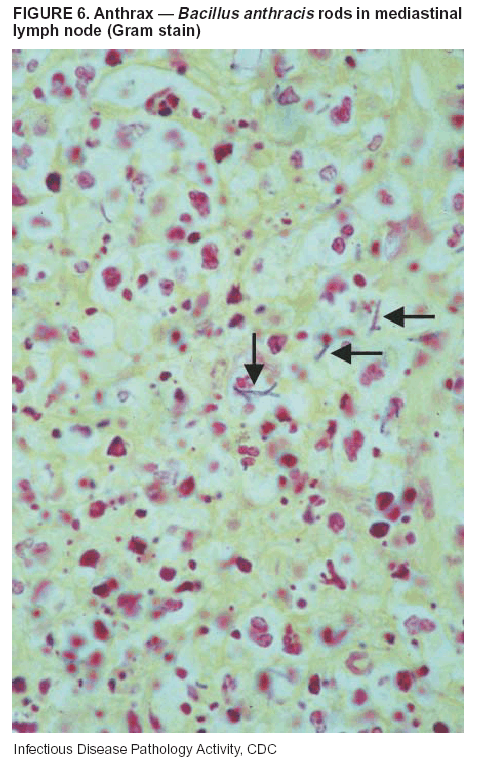

Pathologic Findings. Anthrax has three pathologic forms. Cutaneous anthrax is characterized by an eschar that forms where the bacteria entered the skin (Figure 2). Microscopically, the epidermis has necrosis and crusts, whereas the dermis demonstrates necrosis, edema, hemorrhage, perivascular inflammation, and vasculitis. The lymph nodes that drain the skin site eventually become enlarged, necrotic, and hemorrhagic. Gastrointestinal anthrax is distinguishable by hemorrhagic ulcers in the terminal ileum and caecum accompanied by mesenteric hemorrhagic lymphadenitis and peritonitis. Inhalational anthrax is characterized by hemorrhagic mediastinal lymphadenitis (Figure 3) accompanied by pleural effusions. Histologically, lymph nodes have abundant edema, hemorrhage, and necrosis with limited inflammatory infiltrate (Figure 4) (18,25--29). As any of the three anthrax forms progresses, the bacteria can spread to abdominal organs, producing petechial hemorrhages, and to the central nervous system, producing hemorrhagic meningitis (i.e., cardinal's cap) (Figure 5).

Diagnostic Tests. If the patient has not received antibiotics, bacilli can be observed in tissues with H&E, Gram, and silver impregnation stains and IHC assays (Figures 6 and 7). However, after antibiotic treatment has been instituted, only silver stains and IHC assays will highlight the bacilli. IHC assays for B. anthracis can demonstrate bacilli, bacillary fragments, and granular bacterial fragments in formalin-fixed tissues, even after 10 days of antibiotic treatment. Although a DFA test is available for B. anthracis, it is not used on formalin-fixed tissues.